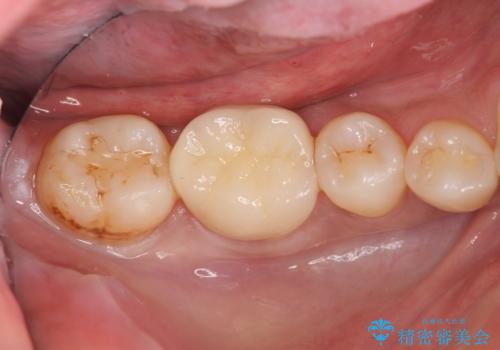

目立つ銀歯が口腔内から取り除かれ、ジルコニアクラウンによる白い歯へと置き換わったことで自信を持って笑えるようになったとの言葉をいただきました。